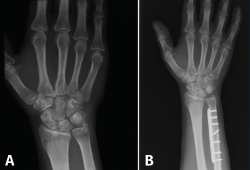

La alternativa más popular a la OAC es la resección parcial del cúbito distal o procedimiento de tipo wafer, con la que se han descrito también buenos resultados tanto de manera abierta (87% buenos o excelentes resultados) como de manera artroscópica (82% buenos o excelentes resultados)(11). Basado en los estudios sobre la modificación de las cargas cubitocarpianas de Palmer(1), Feldon(25) describió este procedimiento de manera abierta en 1992, consistente en resecar una fina oblea de la porción distal de la cabeza del cúbito. Presenta la ventaja, con respecto a la OAC, de que preserva la estructura y la biodinámica original de la ARCD y que no necesita implantar material de osteosíntesis. Prácticamente al mismo tiempo, Buterbaugh(26) describió la técnica de manera artroscópica, que hoy en día es la de elección para realizar un wafer, basado en los mismos fundamentos que la técnica abierta pero añadiendo las ventajas de permitir una completa evaluación diagnóstica de la muñeca, minimizar el daño a la cápsula dorsal radiocarpiana y radiocubital, producir menor dolor postoperatorio y una más rápida recuperación, al permitir una movilización postoperatoria prácticamente inmediata (Figura 5).

Figura 5. A: muñeca con varianza cubital positiva; B: varianza corregida tras wafer artroscópico.

Técnicamente, se realiza usando los portales artroscópicos habituales 3-4, 4-5 o 6R, mediocarpiano radial y mediocarpiano cubital, con los que se realiza siempre una exploración radiocarpiana, cubitocarpiana y mediocarpiana de rigor, para luego limitar selectivamente el trabajo al borde cubital de la muñeca. Aunque no es estrictamente necesario, sí es aconsejable, hasta que se supera la curva de aprendizaje, hacer uso del control con fluoroscopio para confirmar que la resección final de la cúpula de la cabeza del cúbito es la deseada para evitar la impactación. Para realizar la resección, se coloca la cámara en el portal 3-4 o 4-5, y los portales 6R y en ocasiones el 6U se usan para la instrumentación. Inicialmente, si se objetiva una lesión degenerativa central del CFCT, se desbrida con un sinoviotomo para obtener un borde liso, regular y estable. La condromalacia de la superficie de los huesos semilunar o piramidal también se puede tratar con el sinoviotomo.

Una vez realizado el desbridamiento, se podrá observar claramente la cúpula del cúbito y se puede acceder a ella a través de la perforación desbridada. Es importante asegurarse de extirpar el área de impacto de la cabeza cubital por completo. Mediante la pronación y supinación del antebrazo durante el procedimiento se obtiene la exposición adecuada de la cúpula, revelando áreas de la cabeza que pueden necesitar resección adicional.